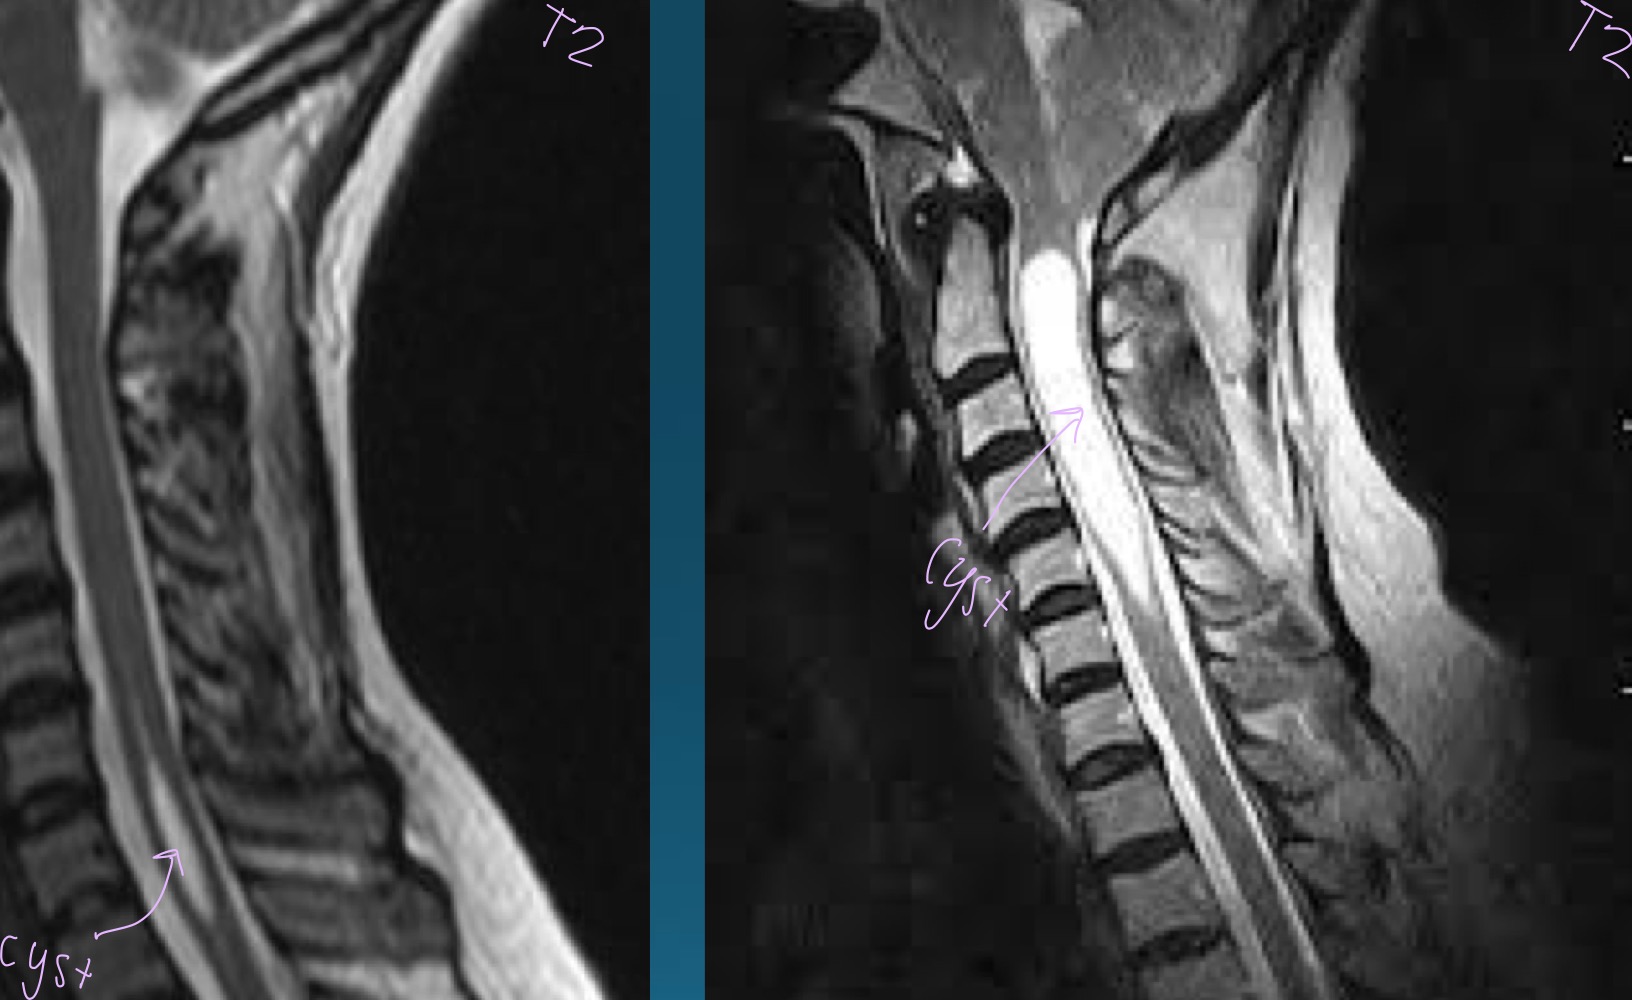

what finding is in this image?

syringomyelia

what would this charcot joint be caused by

syphilis